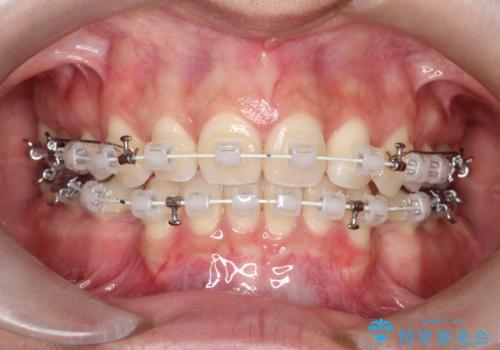

2. 【審美ワイヤー】口元を下げたいの治療中